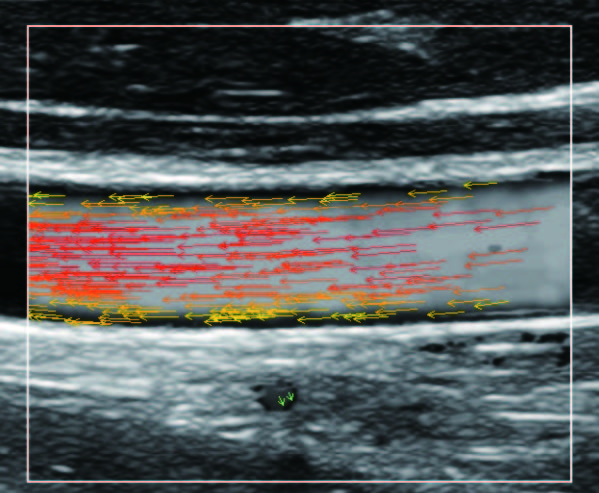

На изображениях, приведенных ниже показаны примеры из клинической практики врачей ультразвуковой диагностики, полученные в процессе апробирования прибора Mindray Resona 7. Приводится наглядные примеры сравнения традиционного режима ЦДК и режима V Flow (Vector Flow).

vflow_5_1.jpg   vflow_5_2.jpg

Изображен ламинарный поток сонной артерии. В режиме ЦДК отсутствует информация о профиле ламинарного потока. Режим V Flow визуализирует не только скоростные характеристики с помощью цветных стрелок, но и предоставляет данные о профиле ламинарного потока (быстрый поток в центре и медленный вблизи стенок сосуда).